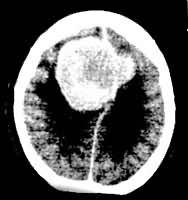

ÄÔ³öѪ£¬ CT±íÏÖΪÄÔÄÚ¸ßÃܶȲ¡±ä£¨Í¼3£©£¬ºÃ·¢ÓÚµ×½Ú¡¢ÇðÄÔÇø£»ÄÔ¹£ÈûÔòΪÀÛ¼°Æ¤Öʼ°ËèÖʵÄШÐεÍÃܶÈÇø¡£CTÒ×ÓÚÕï¶Ï¡£CT»¹¿ÉËæÕï¹Û²ìÄÔ³öѪºÍÄÔ¹£ÈûµÄ²¡ÀíÑݱä¹ý³Ì¡£